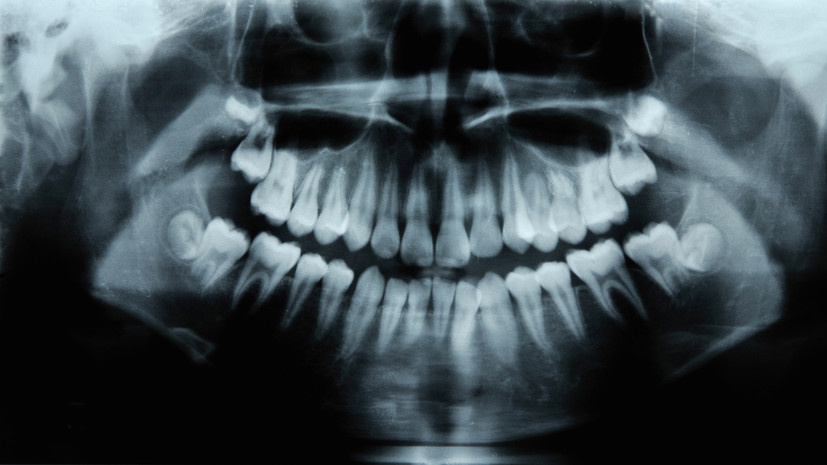

Стоматолог Вольберг объяснил, как меняется лицо после удаления зубов мудрости

Gettyimages.ru

Хирург-стоматолог, имплантолог, пародонтолог Роман Вольберг объяснил, как меняется лицо после удаления зубов мудрости.

В разговоре с «Вечерней Москвой» он отметил, что решение о необходимости удаления зубов мудрости принимает стоматолог после диагностики и постановки правильного диагноза.

«Перед решением об удалении зубов мудрости важно определить, беспокоят ли пациента конкретные симптомы и проблемы. Если в момент обращения у человека отсутствуют жалобы, то достаточно часто в процессе профилактического осмотра и диагностики выявляют наличие зубов мудрости, которые растут в неправильном положении или им не хватает места в челюсти», — подчеркнул эксперт.

Стоматолог объяснил, что из-за позднего появления зубам мудрости часто не хватает пространства для роста, потому что размер челюсти современного человека постепенно уменьшается.

По его мнению, в 99% случаев форма лица после удаления зуба мудрости не меняется, если они не прорезались или встали неправильно в зубном ряду.